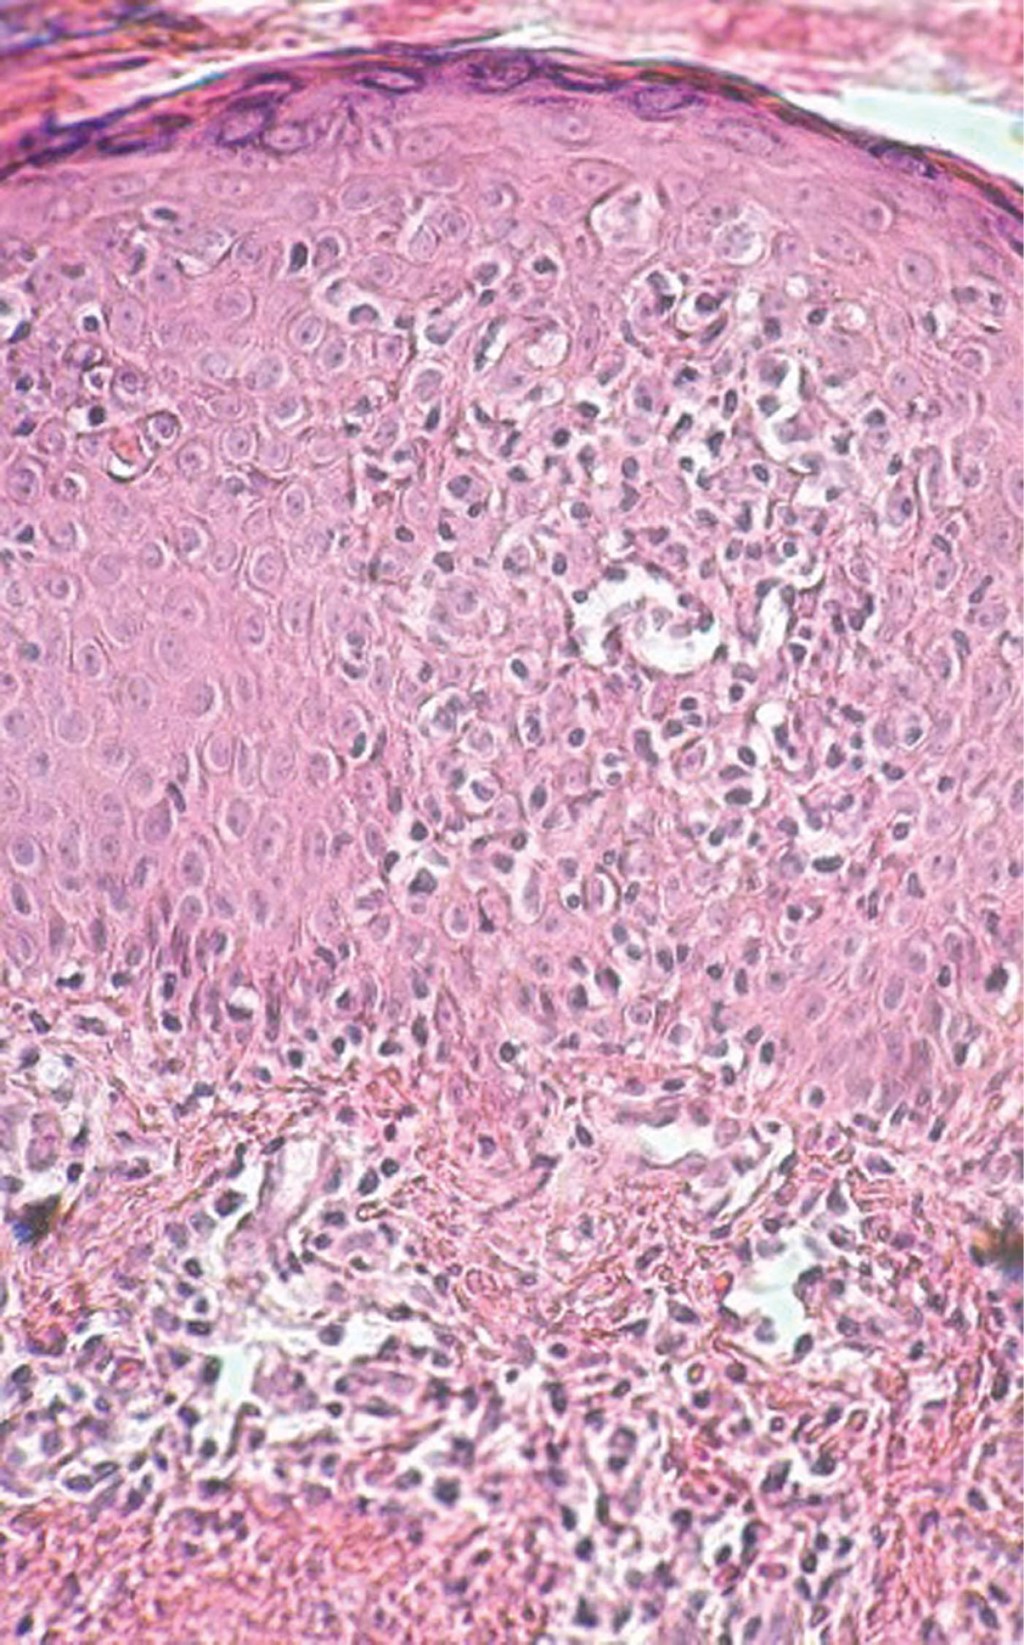

Mycosis fungoides, papular variety

Mycosis Fungoides, papular variety, cutaneous T-cell lymphoma.

Mycosis fungoides is the most common manifestation of T-cell lymphoma at the cutaneous level. At present there are different clinical-pathological varieties. Papular variant was recently described. Its evolution and prognosis vary depending on the time of evolution, being classified as papular mycosis fungoides of "early onset, or late onset". In this article we report the case of a 21-year-old female patient who came to a consultation due to presenting early-onset papular neoformations, diagnosed as papular micosis fungoides, who evolved favorably with the prescribed treatment.

Figure 1